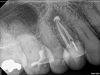

Lastly, regardless of the treatment approach pursued, it is essential to tend to the psychological needs of the patient experiencing a flare-up. The patient should be reassured that the condition is treatable and that flare-ups are quite distinct from treatment failure. In fact, their occurrence has not been shown to affect the overall prognosis of NSRCT (Figure 2 through Figure 5).39,40 Because significant preoperative pain complaints have been associated with a greater risk of flare-up, these patients should be counseled and duly warned of the possible occurrence of a flare-up. Simple discussions on pain management and after-hours emergency availability can significantly reduce the stress of flare-ups for providers and patients alike.14

Fig 2. Case demonstrating successful healing of tooth No. 5 following a flare-up incident. Fig 2: Patient presented with asymptomatic apical periodontitis of tooth No. 5. Fig 3: Following initiation of NSRCT, the patient developed a flare-up with swelling and pain. Amoxicillin was prescribed and the calcium hydroxide medicament was replaced. Fig 4: The patient returned 3 months later with radiographic healing of the apical periodontium. Fig 5: Obturation was completed.

Figure 2